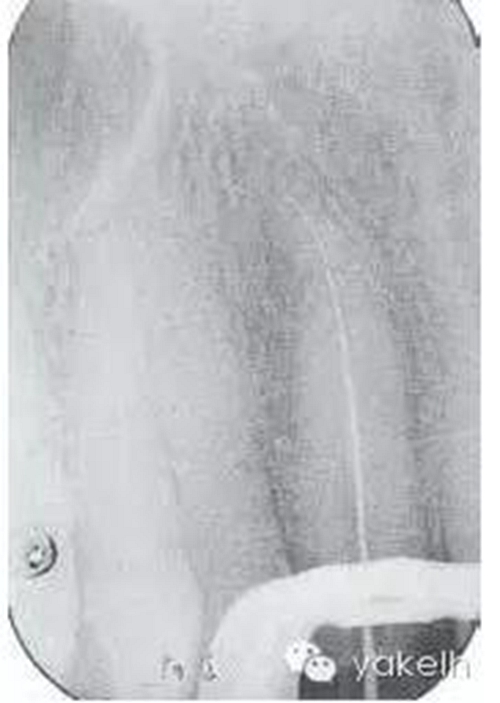

¤¤局麻下,制備上頜切牙印模;拆除12烤瓷全冠;評估患牙的可修復性;橡皮障隔離患牙,定位根管口,使用GG鉆和不銹鋼手用銼去除根管內(nèi)的牙膠;全程使用大量次氯酸鈉沖洗根管;根尖定位儀測量根管工作長度,拍攝X線片確定(圖6.3.3);使用不銹鋼手用銼和鎳鈦旋轉(zhuǎn)器械進行根管預備,EDTA沖洗根管,再用次氯酸鈉進行終末沖洗;紙尖干燥根管;使用牙膠輔以根管封閉劑、采用熱垂直加壓技術(shù)充填根管的根尖5mm;建議樁核冠修復。

圖6.3.3 確定工作長度的X線片顯示,12根管通暢至全長;特征是根管的根尖1/3向遠中腭側(cè)彎曲。